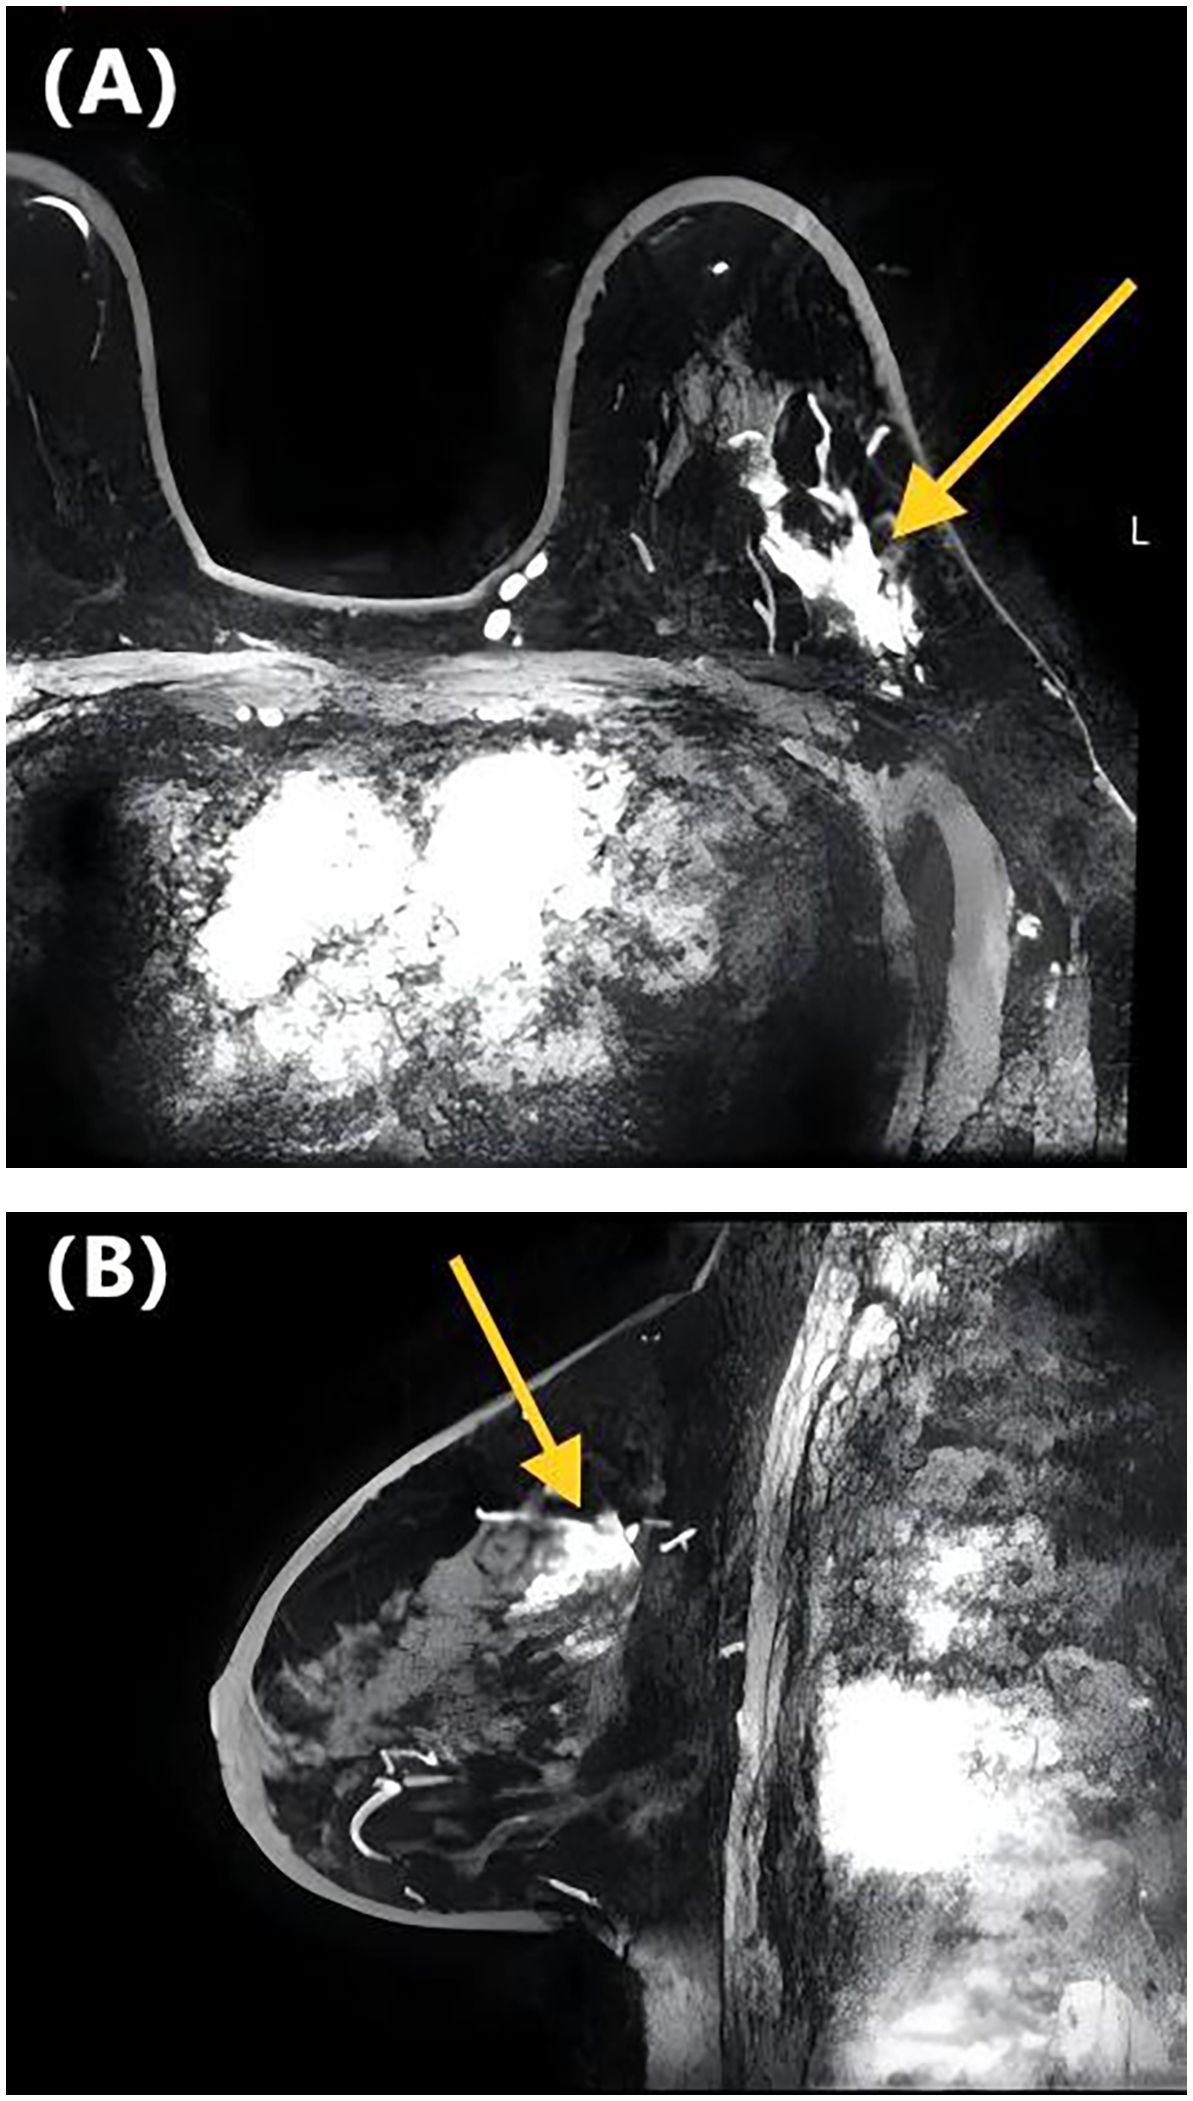

Figure 2. DCE-MRI images of a 65-year-old woman with invasive ductal carcinoma of the left breast. Axial contrast-enhanced image (A) and sagittal contrast-enhanced image (B) show non-mass-like enhancement with the focal distribution. Lymphovascular invasion was negative at the histopathological examination.

Table 2 presents the GVIF analysis used to assess multicollinearity. The regression model demonstrated an absence of significant multicollinearity, as all adjusted GVIF values were below 2.24 except for PR status. Although the GVIF for PR status exceeded 2.24, it remained below the 3.16 tolerance threshold, indicating acceptable collinearity levels. After controlling for confounding factors through multivariate logistic regression analysis, four risk factors associated with LVI formation were identified (Table 3). Patients aged ≥45 years (OR = 0.406, 95% CI: 0.191-0.844, P = 0.017) and those with higher ADC values (OR = 0.133, 95% CI: 0.017-0.825, P = 0.041) had a lower risk of LVI formation. Among the NME distribution patterns, patients with linear distribution had a significantly higher risk of LVI positivity compared to those with focal distribution (OR = 13.540, 95% CI: 1.390-172.644, P = 0.030) (Figures 1, 2), while no statistically significant differences were found for segmental, regional, multiple region, or diffuse enhancement patterns (all P > 0.05). Regarding molecular subtypes, compared to the Luminal A subtype, patients with Luminal B (OR = 5.081, 95% CI: 1.326-33.859, P = 0.039), HER2 overexpression (OR = 9.378, 95% CI: 1.922-71.460, P = 0.012), and triple-negative subtype (OR = 11.599, 95% CI: 2.043-96.710, P = 0.010) had a significantly higher risk of LVI formation.